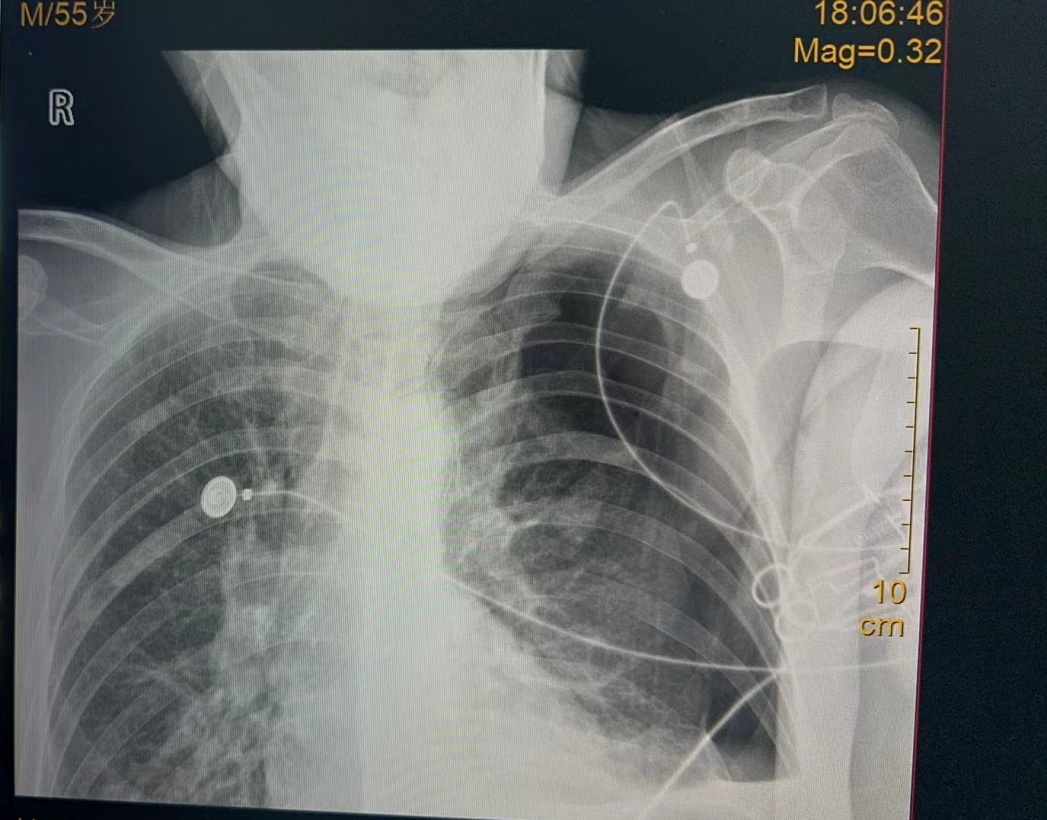

X光機來了,但病人神志已昏迷,無法配合拍片,於是醫護團隊扶助患者坐起,不顧輻射風險,在沒有任何防護措施的情況下全程陪伴病人拍好了胸部X線片。很快,胸片診斷為左側氣胸,需要立刻做胸腔閉式引流術。

胸外科會診醫生迅速開展手術,當針頭進入胸腔的剎那,高壓氣體從胸腔噴出。提示是張力性氣胸。手術順利完成。患者的生命體徵逐漸改善,脫離了生命危險。